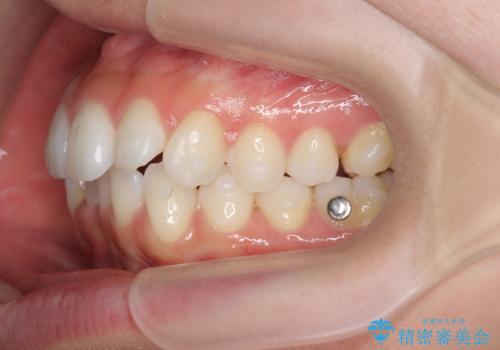

- 前歯が出っ歯のように見えることの改善を求めて来院されました。

当初、セラミックによる治療をご希望されていましたが、相談の結果矯正治療を選択されることとなりました。

通常口元の突出感の改善を行うには小臼歯の4本抜歯が検討されますが、歯のガタ付きが下顎前歯に限定していることから

下顎前歯を1本だけ抜去を行い、上顎の歯は可及的にマイクロインプラントを用いた後方移動を行い口元の印象の改善を計画することとなりました。

マイクロインプラントを用いてしっかりと後方移動を行ったことで前歯の角度は改善され、口元もすっきりと仕上げることができました。